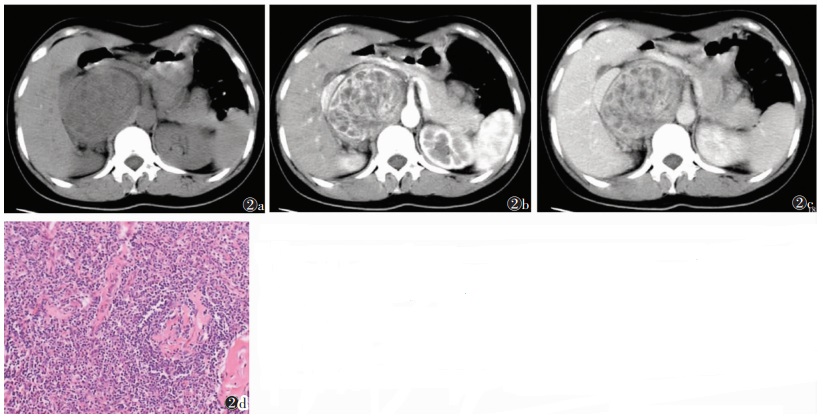

| 图 2 女,25岁,右侧腹膜后局限型透明血管型CD 图2a CT平扫,示右侧腹膜后类圆形肿块,部分边界欠清,密度不均,见斑片状低密度灶,推压周围结构 图2b 动脉期呈不均匀明显强化 图2c 静脉期呈不均匀明显强化,强化程度较动脉期略减低 图2d 病理示中心血管玻璃样变性,周围淋巴细胞呈同心圆状排列,并见大量毛细血管增生(HE×200) |

2 结果 2.1 CT表现10例中,局限型CD 8例,男5例,女3例,病理均为透明血管型,均为单发,其中1例术中见周围增大淋巴结3枚,病理上淋巴结反应性增生2枚,透明血管型1枚。10例中,位于颈部颈动脉鞘旁(Ⅱ区)2例、腹膜后肾脏前上方1例、前上纵隔(与主动脉宽基地相连)2例、后下纵区1例(9区)、右肺门旁1例、右侧盆腔入口腰大肌旁1例。CT平扫呈圆形、类圆形或椭圆形软组织肿块(图 1,2),7例密度均匀(图 1),1例密度不均、内见多发低密度区(图 2),2例伴斑点状、条状钙化,6例边界清晰,1例前上纵隔病灶与主动脉弓宽基地相连、分界欠清,1例右侧盆腔病灶与腰大肌分界欠清。病灶最大径3.3~8.5 cm(平均6.1 cm),2例颈动脉鞘旁及1例肺门旁病灶最大径均 < 5.0 cm,余5例最大径均>5.0 cm,且发生在腹盆腔者相对较大。增强扫描6例中,5例明显强化(图 2b,2c),1例中度强化(图 1b,1c)。4例均匀强化(图 1b,1c);2例不均匀强化(图 2b,2c),静脉期及延迟期病灶内部低密度灶显示明显。4例病灶周围见强化血管影(图 1b)。6例动脉期中度或明显强化、静脉期持续强化呈速升持续上升型或动脉期明显强化、静期强化略下降呈速升缓降型。

2.2 病理结果10例中,透明血管型9例,病理示增生的淋巴组织内散在分布大小不一的淋巴滤泡,滤泡生发中心小,滤泡内血管增生明显伴玻璃样变,滤泡中心淋巴细胞呈同心圆状排列,滤泡间区内见大量毛细血管增生,并见数量不等的浆细胞、嗜酸性粒细胞、组织细胞浸润(图 1d,2d)。浆细胞型1例,病理示滤泡生发中心正常或增大,滤泡间无明显毛细血管增生,有大量浆细胞浸润。